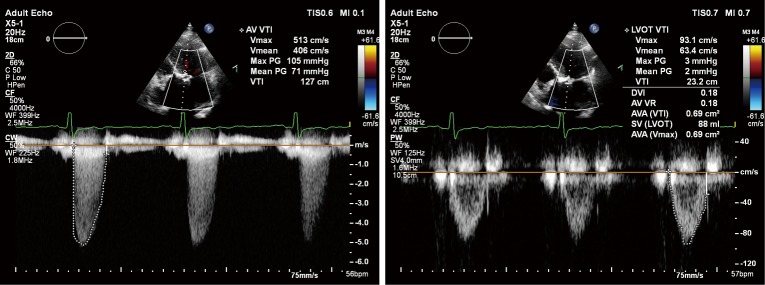

Echocardiography is the primary tool for diagnosis, evaluation and risk stratification of valve disease. As most valve pathology develops gradually over time, echocardiographic screening can deliver accurate detection and risk stratification of patients at all stages of disease. Even when aortic sclerosis rather than stenosis is found (see Figure 3), which is present in one out of four persons aged ≥65 years and nearly half of patients aged >80 years (32,33), this may lead to improved patient care. Although previously thought to be benign, the degree of calcification in aortic sclerosis both predicts risk of progression to AS and also reflects increased cardiovascular risk due to atherosclerosis (34-37). Furthermore, systematic screening with echocardiography in the community not only identifies valve disease but also cardiomyopathy and heart failure. Based on echocardiography performed in >6,000 randomly selected patients aged >45 years from 16 GP-practices in the UK, 26% of patients were diagnosed with VHD and ~3% of patients with unheralded heart failure (38).

Figure 3.

Echocardiology images for aortic valve sclerosis (left panel) and severe aortic stenosis (right panel).